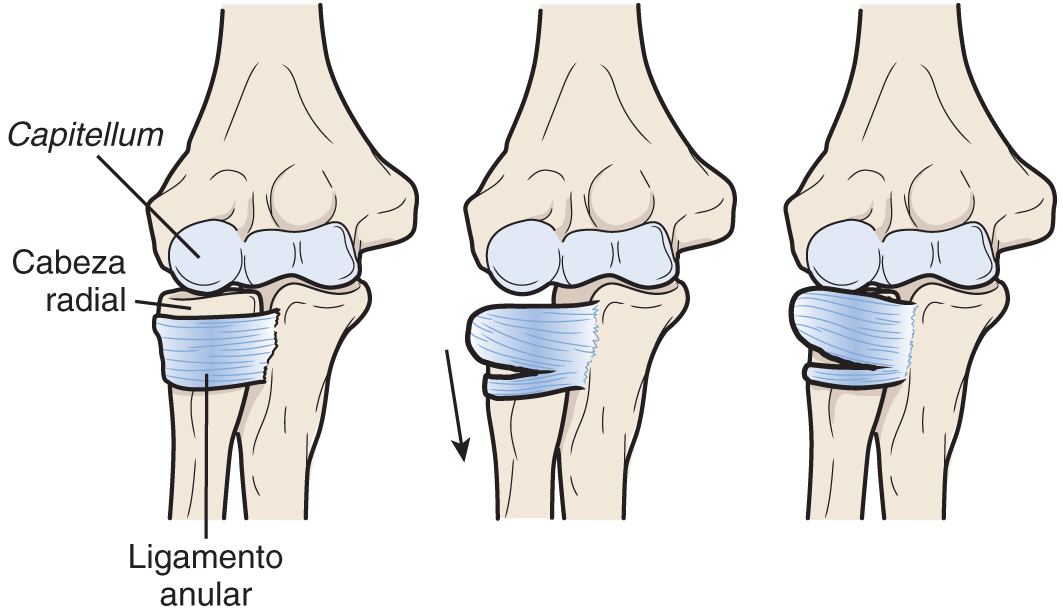

¿Sabéis que es el #CodoDeNiñera o #PronaciónDolorosa? Es una subluxación de la #CabezaRadial. Se produce al aplicar una tracción longitudinal al brazo, que ocurre cuando un niño cogido de la mano se cae o cuando se le levanta por la mano. 📚Nelson. Tratado de pediatría © 2020